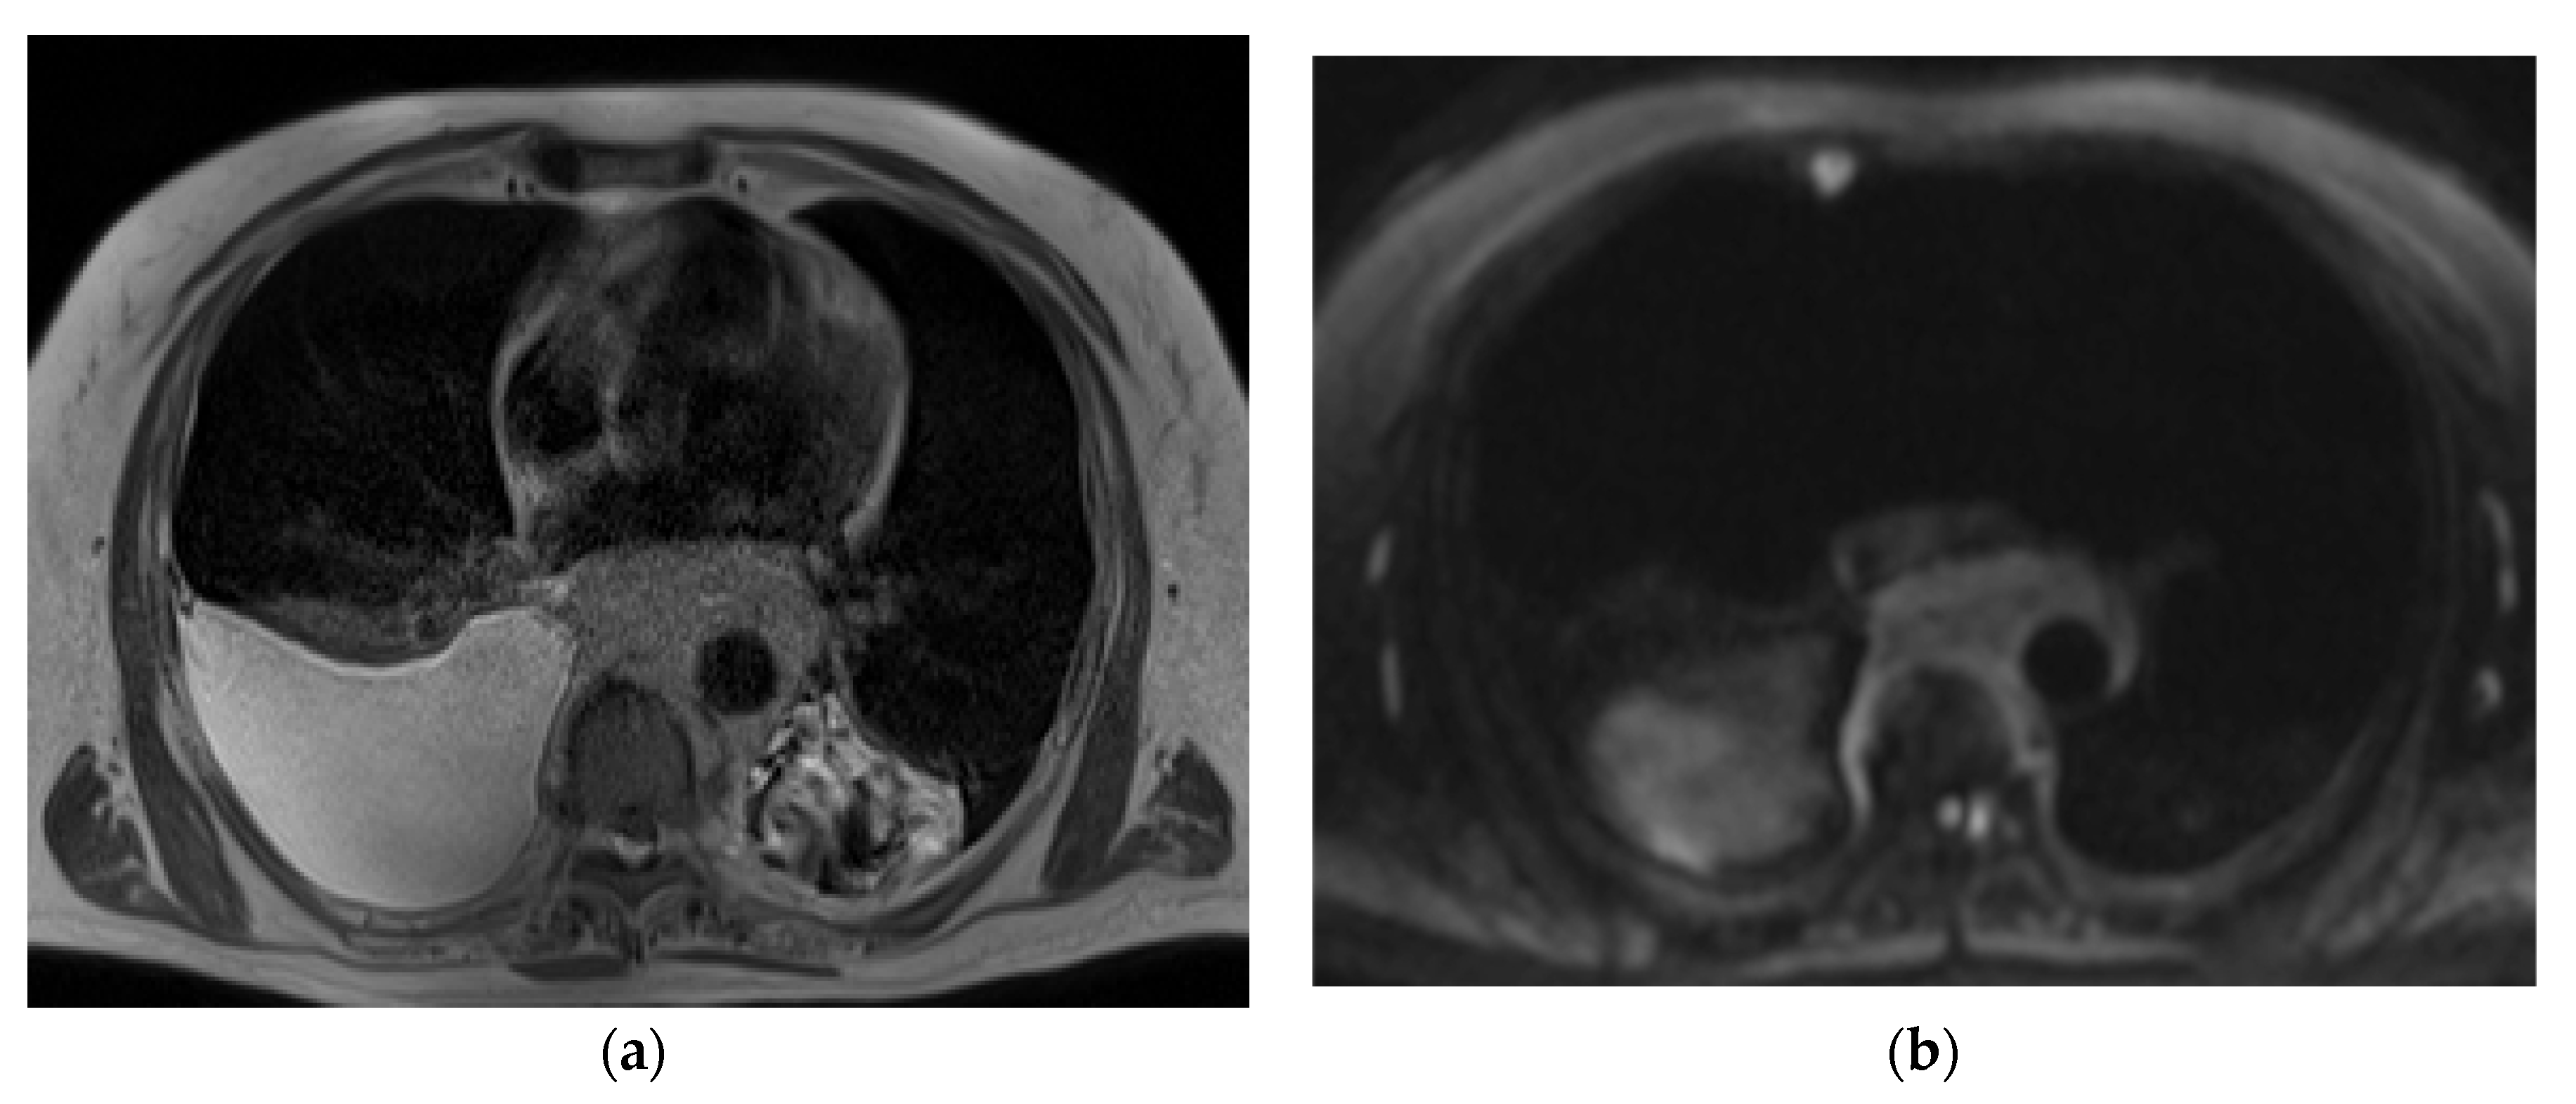

2.4. Image Analysis

2.5. Quantitative Analysis

2.6. Qualitative Analysis